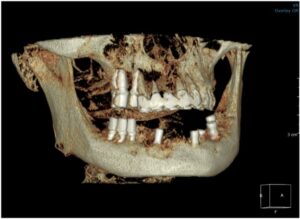

식립 후 2달이 지났을 때

아래턱 앞니와

왼쪽 어금니 부위에

심어둔 임플란트 주변으로

잇몸뼈가 잘 회복하고 있는 것을

확인하였으며

먼저 위턱 어금니와

아래턱 오른쪽 어금니의

지대주 제작을 위한

coping 인상채득을 진행하였는데요.

모든 치료가 마무리된

파노라마 사진과

구강 내 사진인데요.

환자분께서는

치료 후 양측 저작이 편안해지고

심미적으로 변한 모습에

만족해하셨습니다.